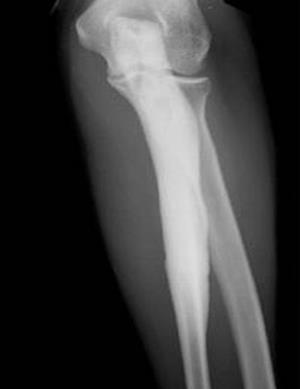

Диагноз можно точно поставить только с помощью рентгена. На нем видны участки, на которых кость сильно уплотнена. К тому же характерна форма таких образований – «стекающая».

Чаще поражаются короткие и длинные, а также мелкие кости руки и ноги. Иногда затрагиваются лопатки или кости таза. Уплотнение обычно не затрагивает всю кость, а только отдельные ее участки.

Также у больного часто отмечают гиперостоз кости.